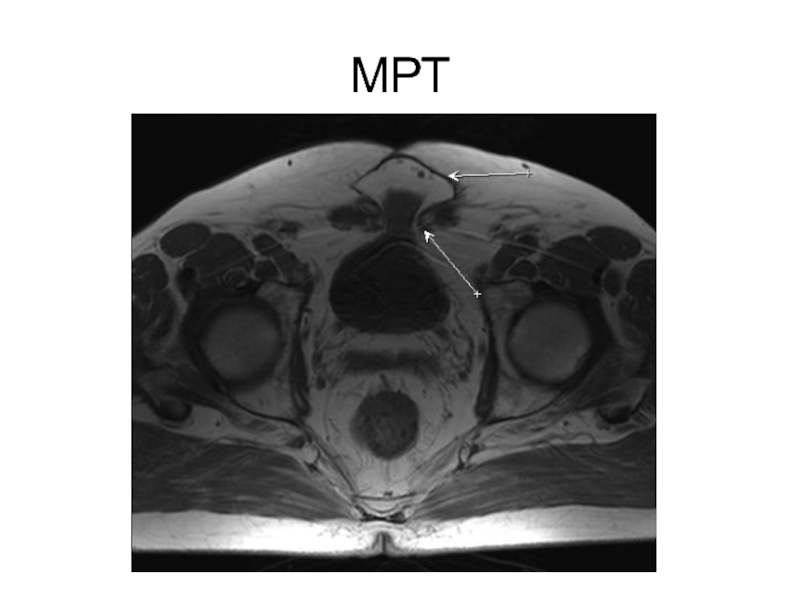

Слайд 13Компьютерная томография

Компьютерная томография